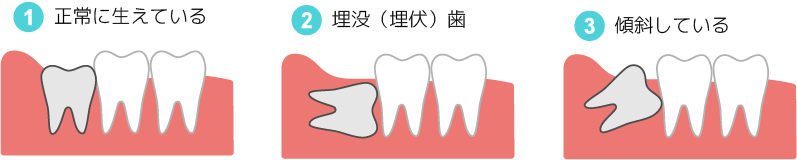

口腔外科

親知らずの痛みや腫れ、顎の痛み、

お口の中の出来物などの治療を行います。

歯・歯ぐきに限らず、口の中・顎・顎の下の疾患全般

(顎関節症、口腔の腫瘍・のう胞、舌小帯異常など)の診断・治療、

骨の中に埋まった親知らずの抜歯(難抜歯)などをおこないます。

主に外科的処置をおこないます。

(全身疾患がある場合は出来ない場合があります。)

親知らずの移植

ほかの奥歯がむし歯や歯周病、破折などで抜歯となる場合、親知らずをその場所に移植します。